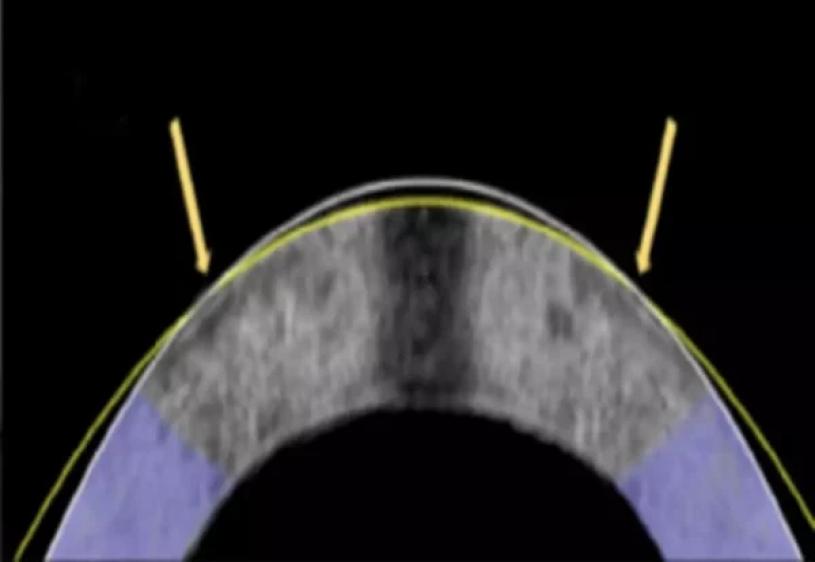

相比之下,EMR的思路截然不同。角膜主要由膠原蛋白纖維組成,這些纖維排列與分子電荷共同維持其形態。研究人員利用特製的鉑金電極「隱形眼鏡」,於角膜表面施加低強度電流,暫時改變局部的酸鹼值,使組織變得柔軟,可以像塑膠般被壓模成新形狀。當電流停止,酸鹼值回復正常,角膜隨即重新硬化並固定在新的弧度之上,整個過程僅需約一分鐘,無需切割或移除任何組織。

在早期實驗中,研究團隊將此技術應用於12隻兔眼,其中10隻成功獲得矯正,角膜弧度的改變相當於改善約三百度近視。更重要的是,檢測顯示角膜並無細胞死亡或結構性損傷,顯示出高度安全性。研究人員指出,這項方法或能取代激光手術,為矯視帶來更便宜、更安全,甚至可逆轉的選擇。